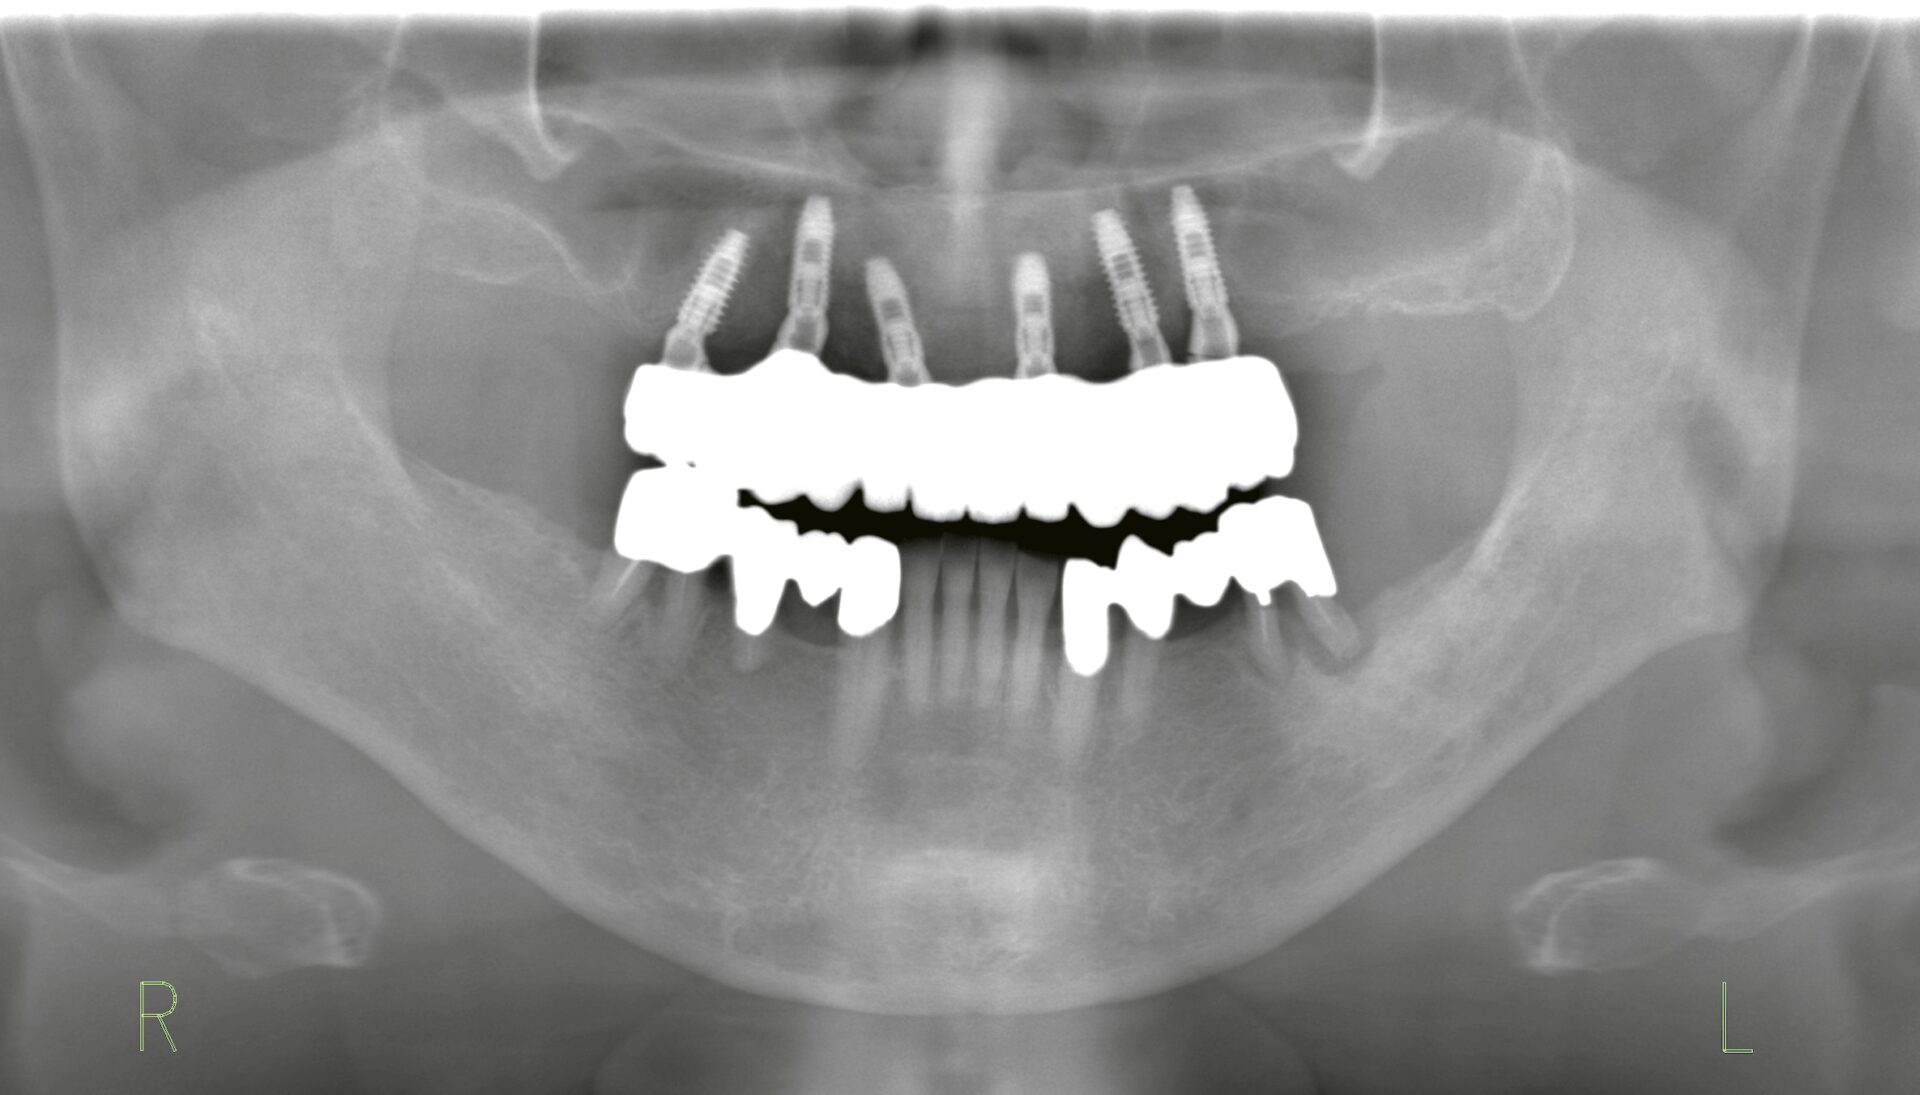

オールオン6による固定式ブリッジ

| Treatment plan | オールオン6による固定式ブリッジを計画。即時荷重を前提とし、審美性・咀嚼機能・心理的安定を同時に回復することを目的としました。 |

1. 初期治療(Day 0) ・インプラントを6本埋入。 ・そのうち5本で即時荷重による固定式の仮歯を装着。 2. 3ヶ月後 ・仮歯の交換を実施。咬合や形態を調整し、安定した機能と審美性を維持。 3. 6ヶ月後 ・骨造成部位の二次オペを実施。 ・最終補綴としてジルコニアベースのフルアーチブリッジを装着。長期的な耐久性と審美性を確保。